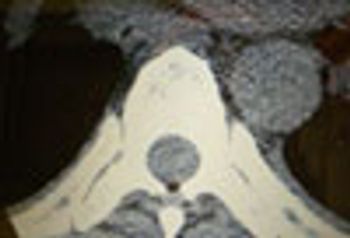

Spinal problems include epidural abscess, paravertebral muscle atrophy, Chiari I malformation, osteomyelitis/discitis, diastematomyelia, spinal compression, spinal tuberculosis.

An obese woman in her thirties with a history of fibromyalgia syndrome, depression, polycystic ovarian syndrome, and diabetes mellitus presents to her local emergency department with 1 week of gradually worsening midline back pain.